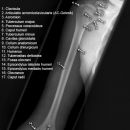

Oberarm lateral (2. Ebene)

Fraktureinteilung

der proximalen Humerusfrakturen (2) nach Neer (modifiziert):

Einteilung des Humeruskopfes in vier anatomische Segmente: Kopf, Tuberculum majus, Tuberculum minus, Schaft

- Typ I (85%): Jede Fraktur bei der keine Dislokation >1cm oder >45° vorliegt

- Typ II: Frakturen des Collum anatomicum (>1cm oder >45°); können bei inadäquater Aufnahmetechnik (Innenrotation!) leicht übersehen werden: GEFAHR der Humeruskopfnekrose!

- Typ III: Fraktur im Collum chirurgicum (>1cm oder >45°)

- bei Typ IV: Dislozierte Frakturen des Tuberculum majus gehen immer mit einer Rotatorenmanschettenruptur einher! Bei Abriss des Tuberculum maius rotiert das Kopfragment durch den Zug am Tuberculum minus (M. subscapularis) nach dorsal. Das abgerissene Tub majus disloziert durch den Zug der Außenrotatoren nach kranial und dorsal.

- Bei Typ V: bei Abriss des Tuberculum minus rotiert das Kopfragment durch den Muskelzug am Tub. maius (Außenrotatoren) nach ventral => "Vollmondzeichen", das abgerissene Tuberculum minus disloziert nach ventromedial.

- Bei Kindern regelhaft Epiphysenlösung, meist mit metaphysärem Fragment (Salter II)

der Humerusschaftfrakturen (2):

- Indirekte Gewalt => Spiralverletzung, Direkte => Quer-/Biegungs-/Stückfraktur

- In ca. 25% liegen Begleitverletzungen in der Schulter und des Unterarms vor! (Im mittleren Schaftdrittel: in 10% Radialisparesen)

- Frakturen proximal des Deltoideusansatzes: Dislokation des proximalen Fragments nach medial (Pektoraliszug), des distalen Fragments nach lateral (Deltoideuszug)

- Frakturen distal des Deltoideusansatzes: Dislokation des proximalen Fragments nach lateral (Zug des M. deltoideus und M.coracobrachialis), des distalen Fragments nach proximal (Zug des M. biceps und M. triceps)

der distalen Humerusfrakturen (vgl. Ellbogen):

- Bei Erwachsenen in 90% Gelenkbeteiligung

- Bei Kindern meist suprakondyläre Frakturen (Cave Knochenkerne!)

- Bei disloziertem Fragmentabscherungen am Capitulum humeri oder der Trachlea => „Halbmondzeichen“ durch konvexbogiges Fragment

- Verlagerung der ventralen und dorsalen Fettkörper (intraartikulär), Hämarthros